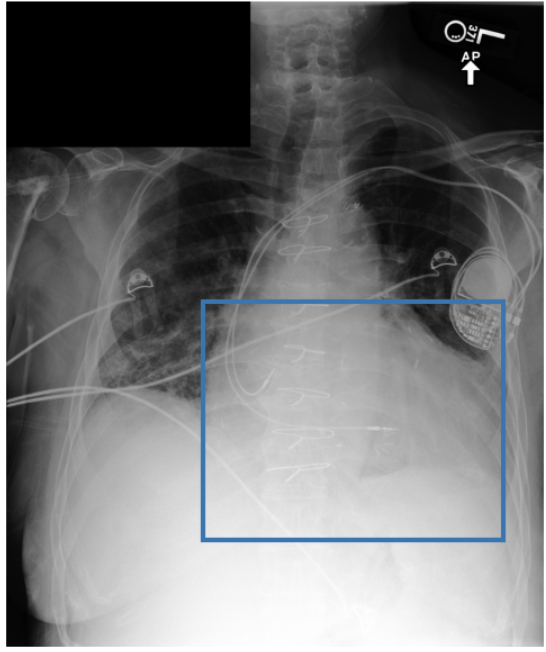

Figure 3 shows phrase grounding results for the phrase “Chronic inflammatory changes predominantly in both lung apices” on an image from PadChest-GR [11]. Both CURE and MAIRA-2 successfully identify the lung apices associated with the described findings. However, CURE’s localization is more accurate and better aligned with the phrase semantics, while MAIRA-2 provides a coarser prediction that only partially covers the relevant areas. As expected, MedGemma-4B-IT does not produce visual grounding outputs, and thus no bounding boxes are shown for this model.